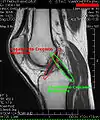

MRI

Both anterior cruciate ligament (ACL) and posterior cruciate ligaments (PCL) are hypointense on both T1 and T2 weighted images of MRI. However, some high signal striations are often seen at the distal part of the ACL, making ACL higher intensity than PCL on MRI scans.[17]

Knee MRI (PD TSE FS sagittal)

Knee MRI (T1 TSE sagittal)- Knee MRI (sagittal TSE FS)